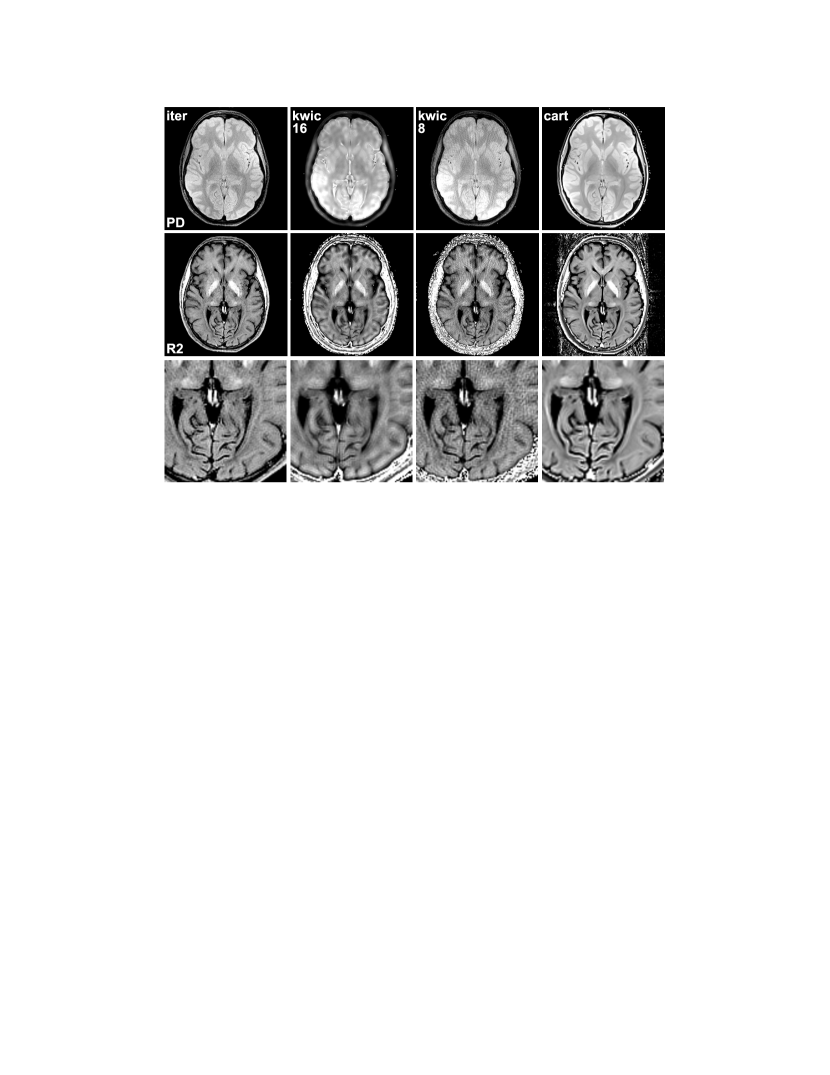

Figure 2 shows corresponding reconstructions for a transverse section of the human brain in vivo. Again, the KWIC reconstruction using 8 echoes suffers from streaking artifacts, while the maps involving all echoes appear fuzzy and blurry. In the latter case, the spin-density map is further contaminated by sharp hyperintense structures. This results from padding the high frequencies with data from late echoes which introduces components with T2 weighting and poses a general problem when sharing data with varying contrast. The iteratively calculated maps present without these artifacts. For comparison, maps from a fully-sampled Cartesian data set are presented, which show good agreement with the maps obtained from the iterative approach. Noteworthy, because the slice thickness was higher in the Cartesian acquisition, these maps show a slightly larger part of the frontal ventricles, which, however, is not related to the reconstruction technique.

For the same radial data set, Fig. 3 compares snapshots of the first, 6th, and last echo reconstructed using the proposed method with Eq. (14), direct gridding, and KWIC with sharing of 8 echoes. Corresponding images from the Cartesian data set are shown as reference. The contrast of the Cartesian and gridding images can be taken as ground truth due to the equal echo time of all k-space data used. It can be seen that the snapshots calculated with the proposed method show good match to the contrast of the Cartesian gold standard while they are not affected by streaking artifacts.